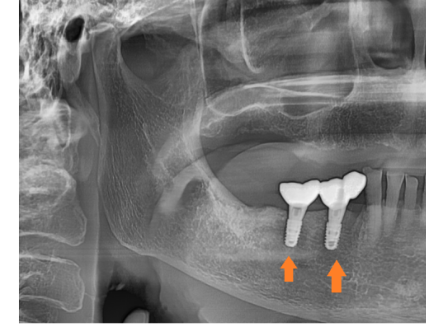

늘 분석합니다.

수술 전 불안해하시는 분들이 많은데요,

강동구 임플란트를 위해 의료진은 늘 준비합니다.

시뮬레이션을 하고

문제가 생겼을 때 대응책도 준비되어있어요.